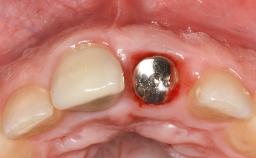

In this case, Mario Roccuzzo utilizes surgical bone regeneration treatment around implant 46 using a bone graft substitute and a connective tissue graft to resolve peri-implant inflammation, reduce the probing depths, and prevent further progression of disease.

A 58-year-old-male patient was referred in February 2007 for implant placement in the right mandibular molar area. Two tissue level implants were inserted at sites 44 and 46, respectively, to support a three-unit fixed dental prosthesis (FDP).